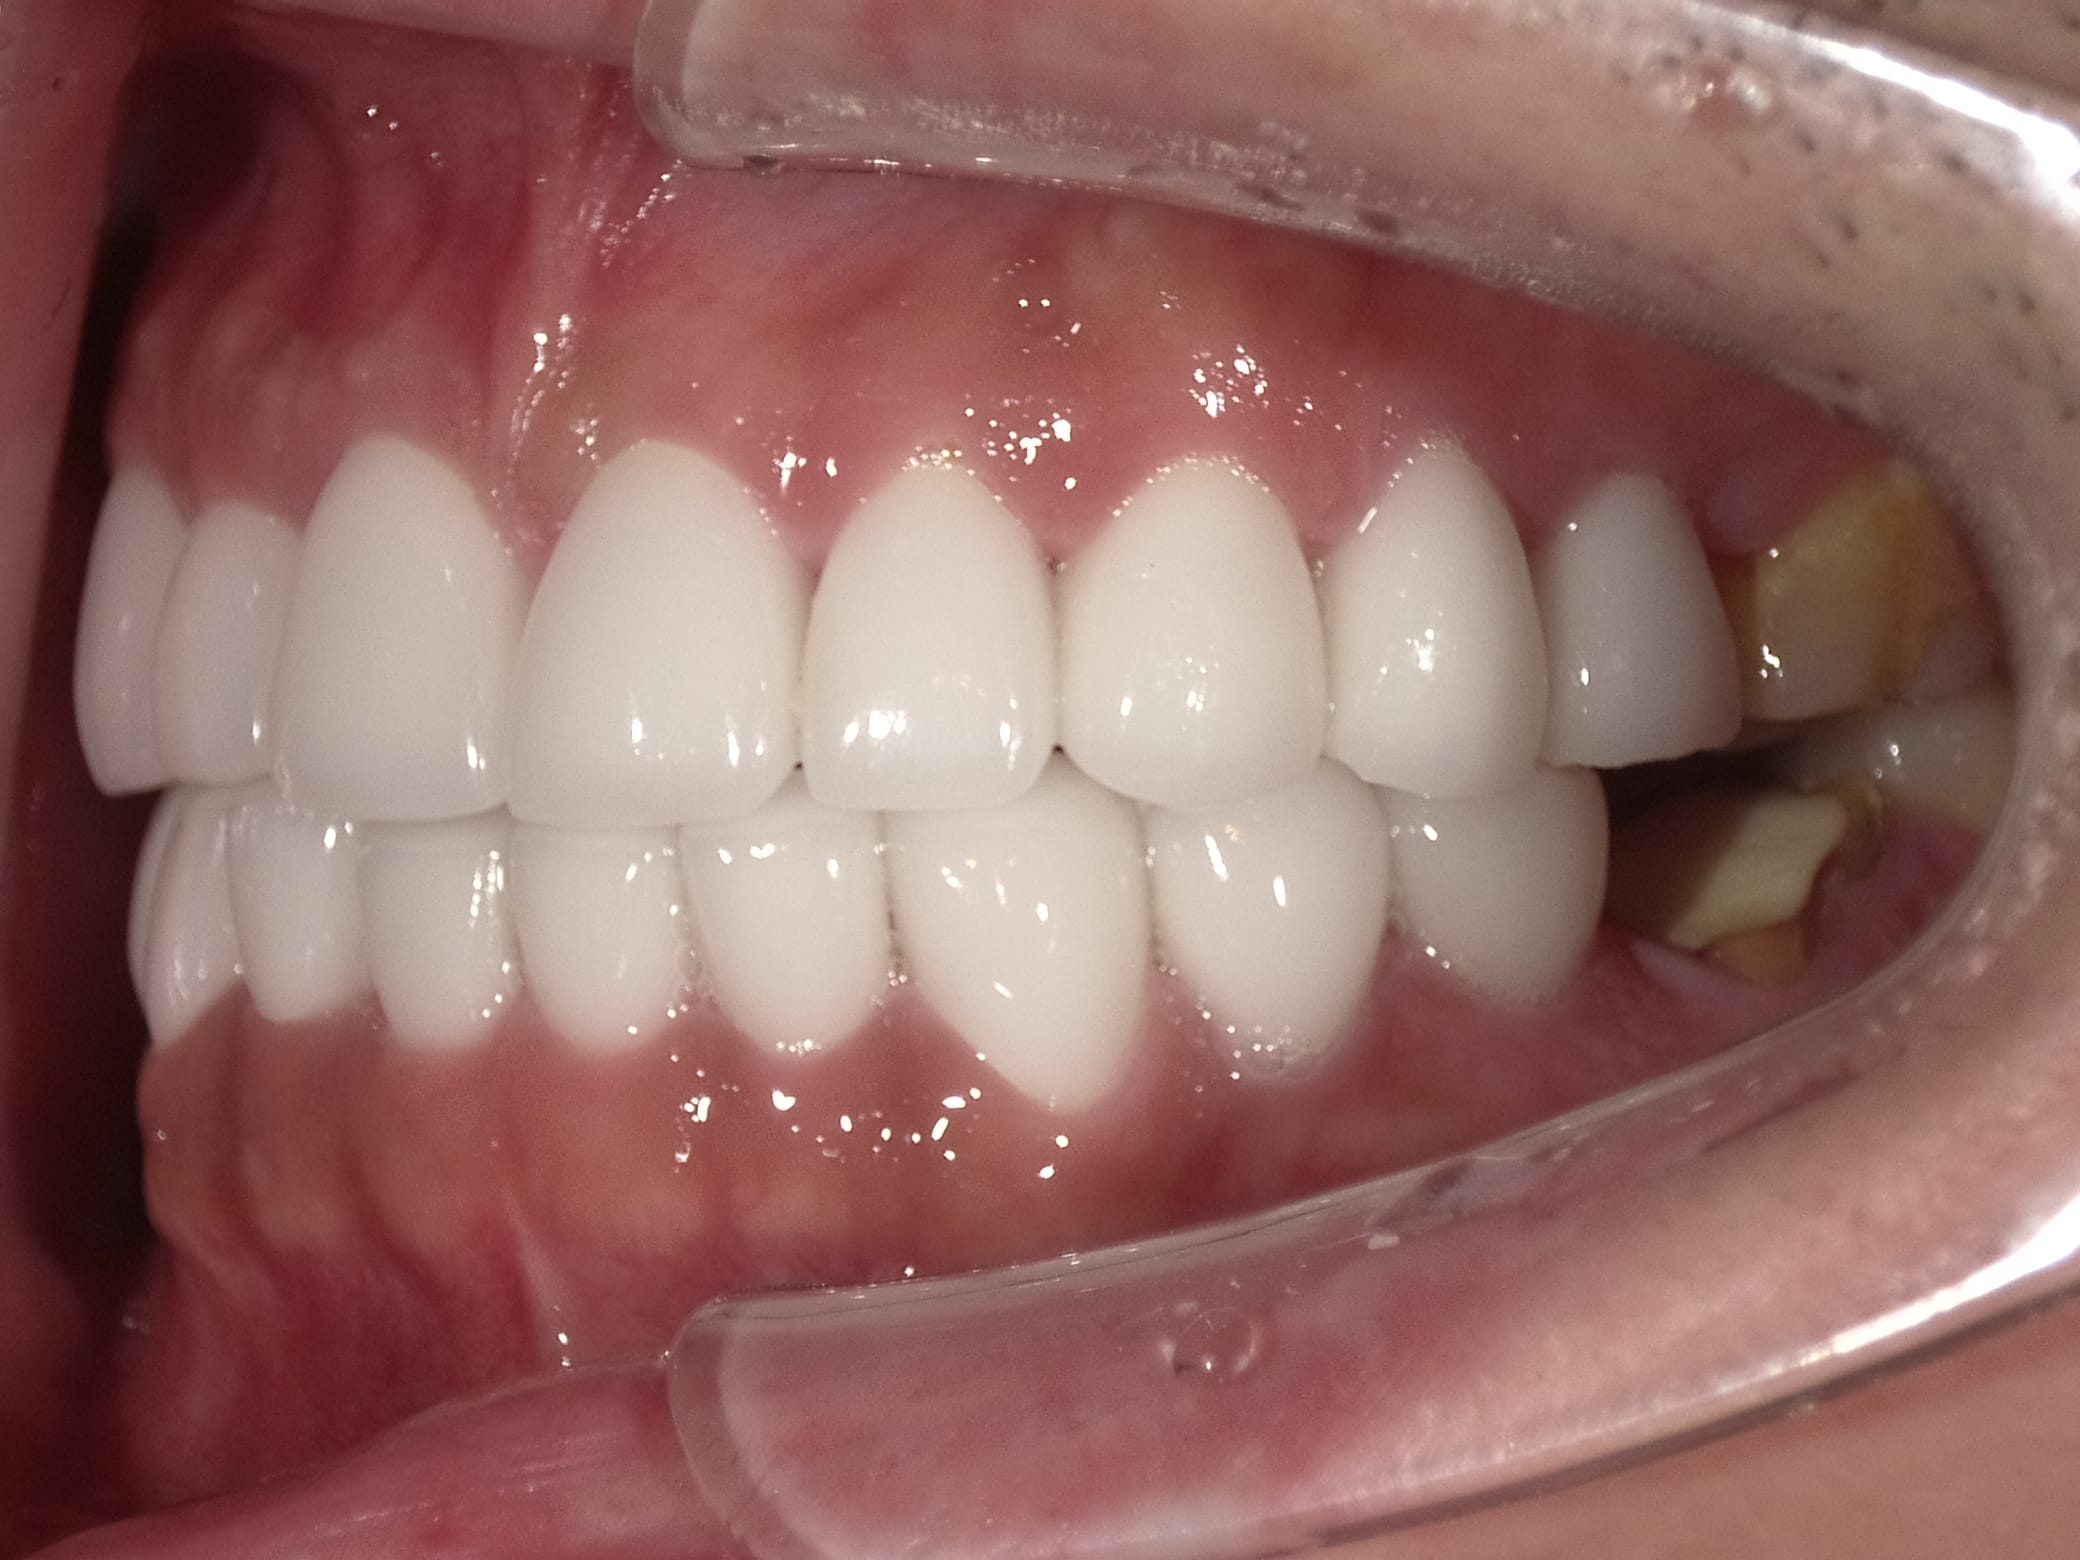

Case034

広島からの患者様です。

前歯を綺麗にしたい。インプラントをしたい。

という主訴で東京の歯医者をいろいろ調べて当院を選んでくださいました。

毎回、遠い中しっかり通ってくださり、選んで頂けた嬉しさと、その気持ちに応えたいという想いで診療させて頂きました。

前歯はご希望のお色でラミネートベニアでは出せない透明感のあるセラミックに上下左側7はインプラントをさせて頂きました。

左上は破折で温存不可。

骨も少なかったので、サイナスリフトも行い計五回の来院で被せ物を入れさせて頂きました。

左下は前回のクリニックでの埋入位置が深すぎて食べカスも毎回詰まる、セルフメンテナンスではら汚れも取れない。インプラント周囲炎にもなっていたので、一度前のインプラントを除去し、そこから新しくインプラントを埋入し、診療させて頂きました。

インプラント、歯並び、審美歯科にご興味のある方はいつでも相談にお越しください。

担当 理事長 佐藤 悠野